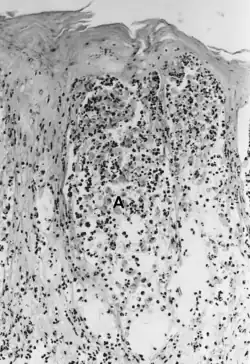

| Foot-and-mouth disease - acantholysis in a sample of a skin vesicle: Necrosis of the stratum spinosum can be observed, and keratinocytes floating in the vesicular fluid (spongiosa). | |